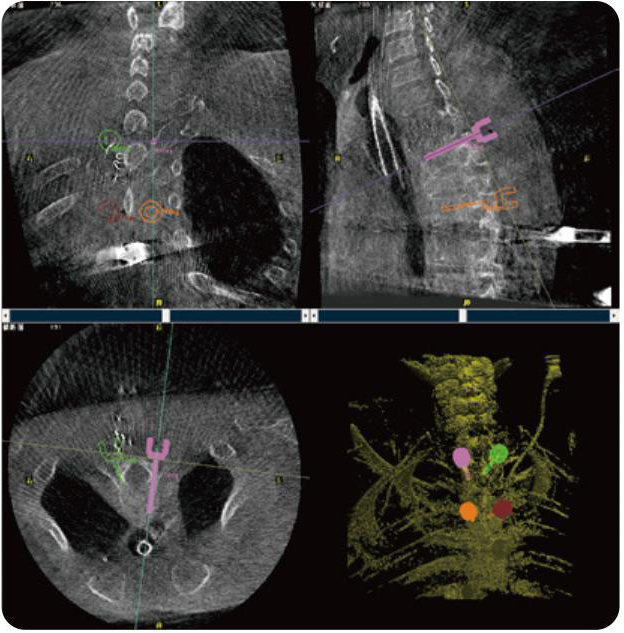

PL300B可應(yīng)用于多節(jié)段脊柱外科手術(shù),輔助醫(yī)生定位病灶部位,為脊柱外科手術(shù)(經(jīng)皮椎體成形術(shù)、椎弓根螺釘內(nèi)固定術(shù)等術(shù)式)提供術(shù)前手術(shù)流程規(guī)劃、入釘位置、角度可視化引導(dǎo),模擬仿真入釘輔助。

PL300B搭配普愛醫(yī)療自主研發(fā)生產(chǎn)的平板3D C形臂,借助一體化自適應(yīng)配準( 軌跡配準)技術(shù),通過追蹤C形臂三維采集軌跡,自動完成圖像坐標建立和系統(tǒng)坐標配準。配準精度更高,操作步驟少,系統(tǒng)運作效率高。